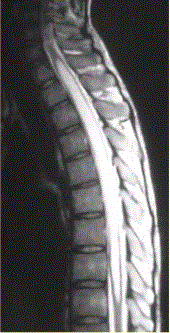

问题 患者女,45岁,胸部不适。影像学检查结果如下图所示。 病变的诊断为

选项 A.星形细胞瘤 B.室管膜瘤 C.脊髓空洞 D.髓内寄生虫 E.成血管细胞瘤 F.脊髓内转移瘤

答案 E